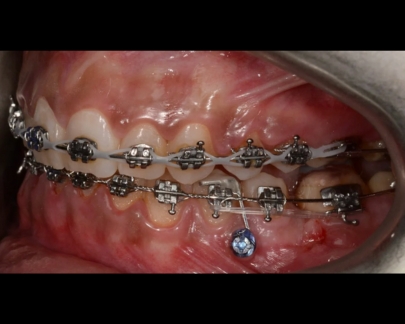

Sunt benzi elastice mici, din latex, folosite pentru corectarea mușcăturii și intercuspidarea dinților.

Elasticele se atașează de brackeții dinților superiori, respectiv inferiori și vin în diferite dimensiuni și grade de forță.

![]() | ![]() |

Elasticele ortodontice corectează raportul dintre maxilar și mandibulă (mușcătura). Sunt purtate conform indicațiilor medicului și sunt esențiale în multe tratamente pentru alinierea corectă a arcadelor.